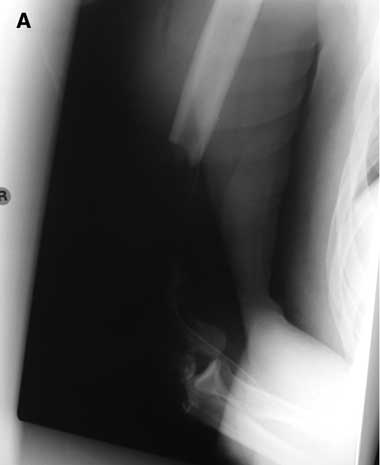

The most severe upper-arm injury involved Patient 7, with loss of the right distal humerus and olecranon, combined with an ulna nerve injury (Box 3). Initial treatment consisted of debridement and application of a bridging external fixator across the lost elbow joint (Box 4). This was complicated by iatrogenic radial nerve neuropraxia caused by the insertion of a Steinman pin. The external fixator was later replaced by a humeral allogeneic bone graft, an elbow prosthesis, and plate fixation of the humeral shaft (Box 5). The same patient also subsequently underwent a revision of the humeral plate procedure after a deep infection with Staphylococcus epidermidis was identified.